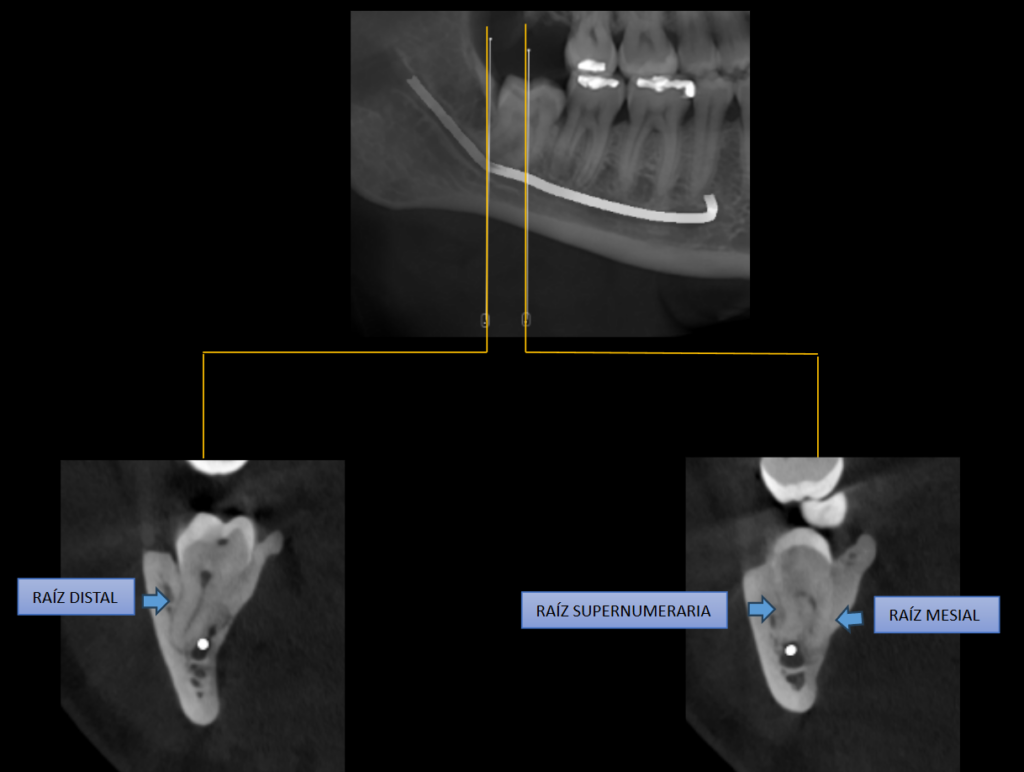

A la evaluación de la tomografía computarizada del motivo de consulta que fue la pieza 48 se observa impactada contra la superficie cervicodistal de la pieza 47, asimismo se observa la presencia de una raíz supernumeraria por vestibular y por mesial (paramolaris), la

hipercementosis de los tres segmentos, así como la dilaceración de los mismos a predominio de la raíz supernumeraria. Finalmente, el conducto dentario inferior recorre por lingual de la raíz distal y por el medio de ambas raíces mesiales, contactando con los ápices.